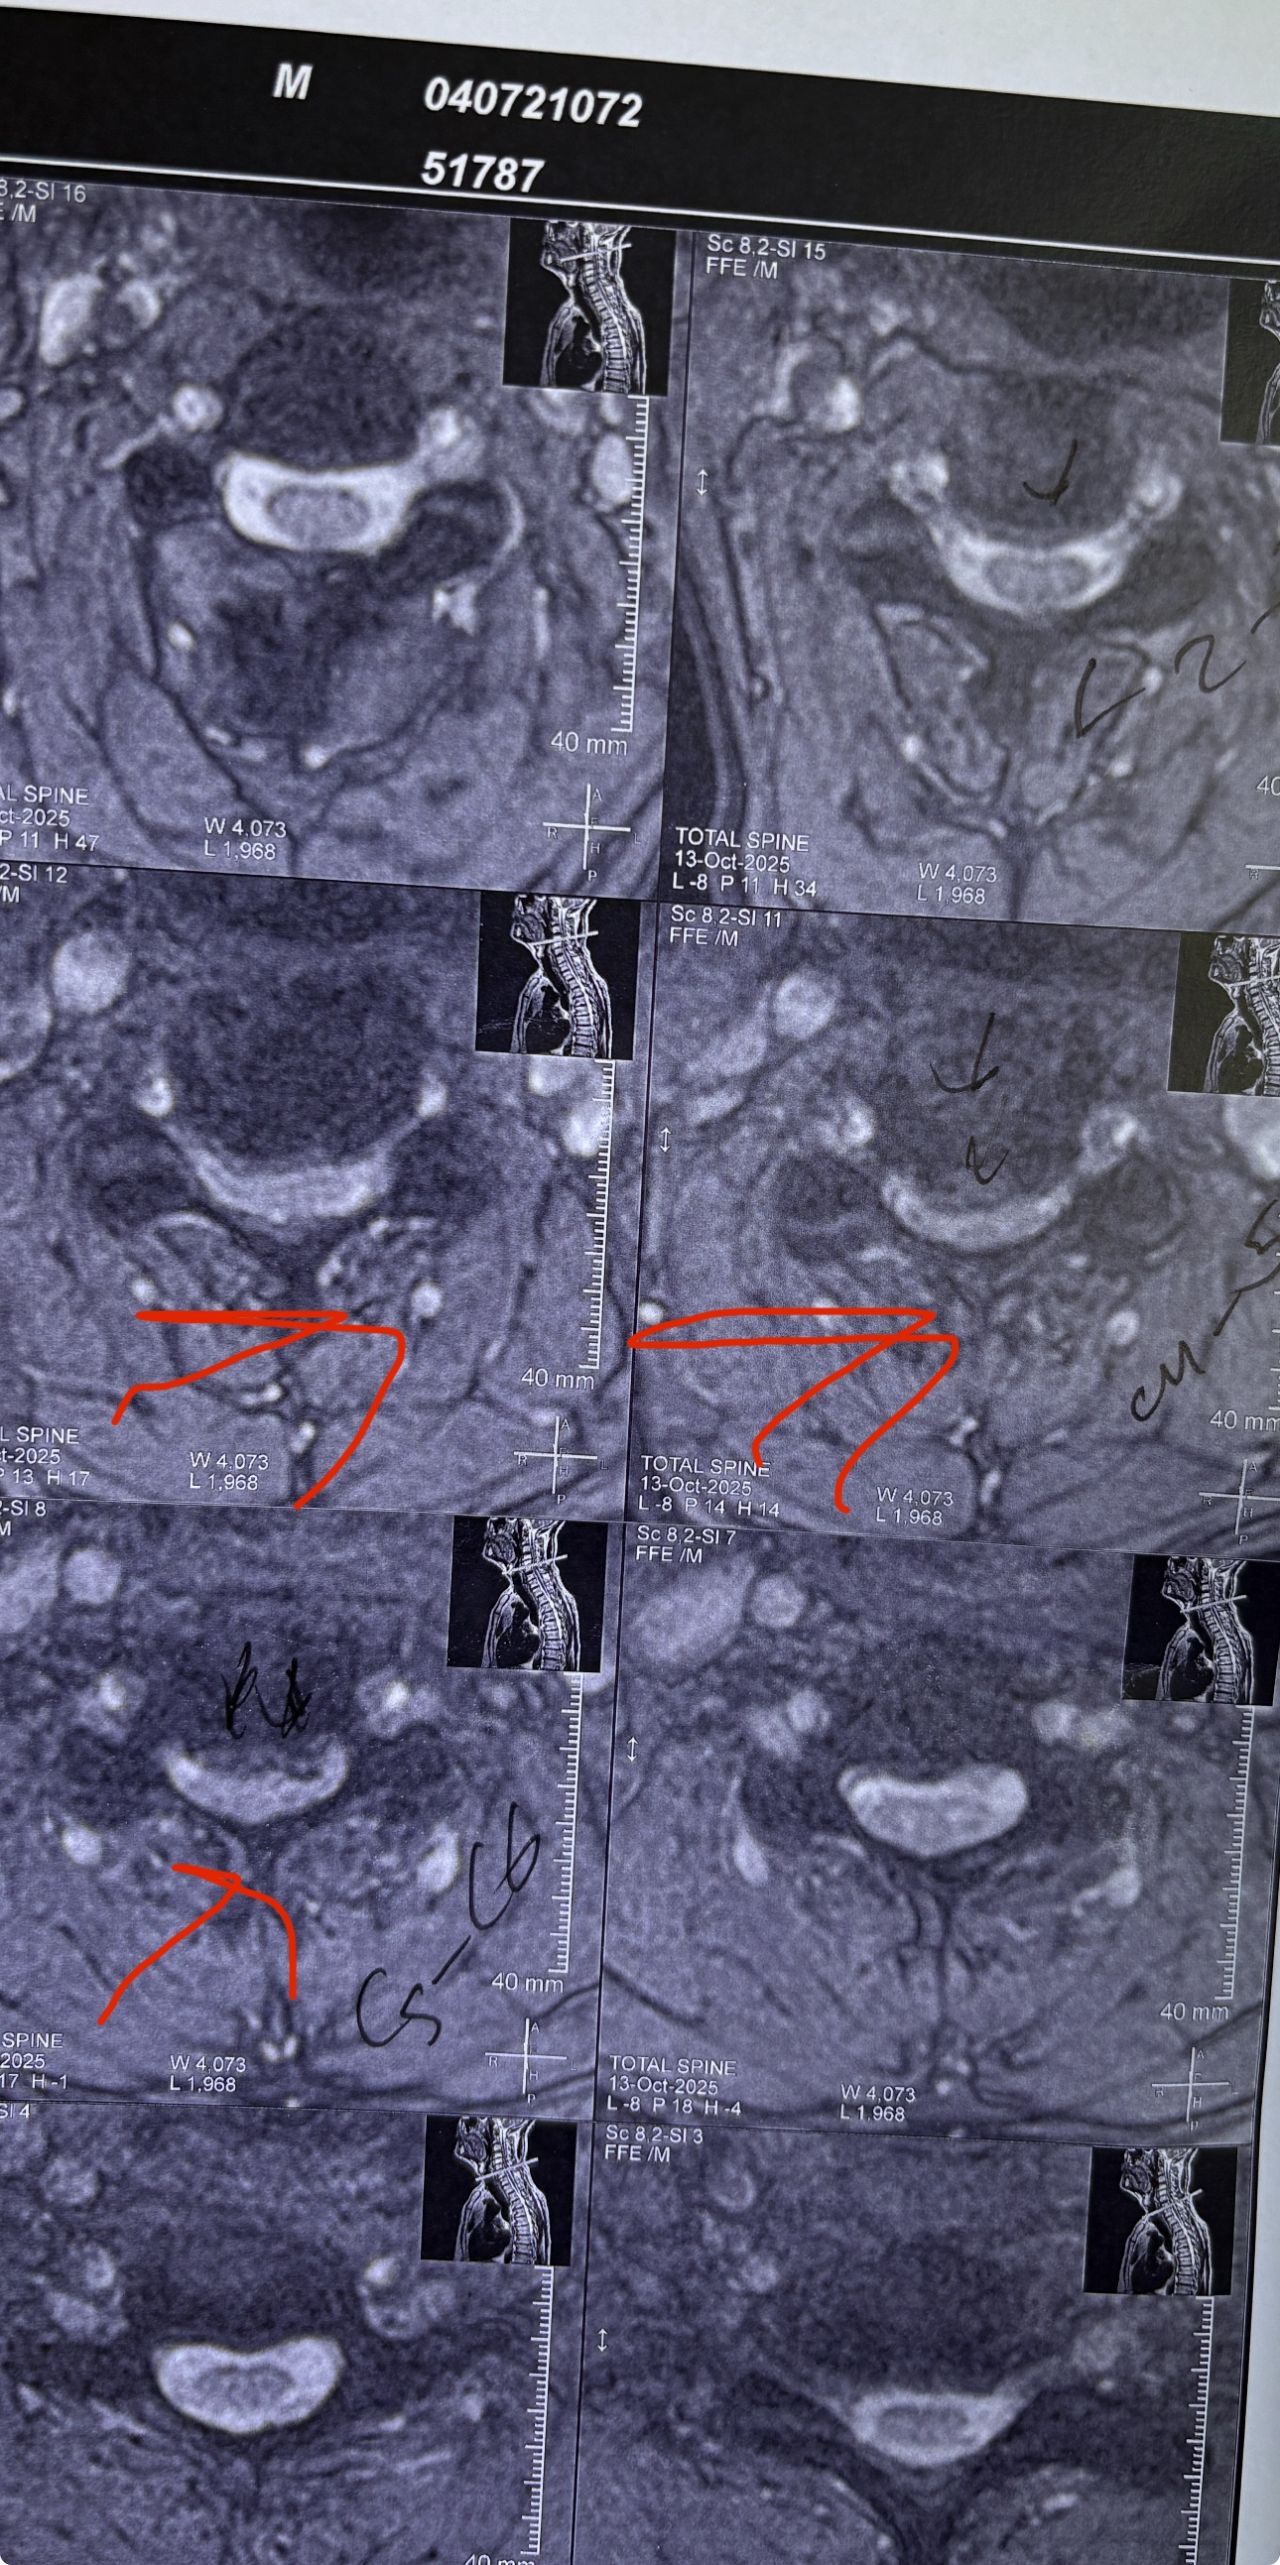

40 yrs old male patient presented to my office who had severe R gluteal pain and radicular pain along R L5-S1 now pain has reduced by 80% in his motor exam had R big toe L5 motor reduced to 4+\5 and R S1 DTR was 0 while L S1DTR was 1+

We did EMG/NCV which showed Mod- sever R L5 S1 irritation without any active axonal loss

I had to decide to refer him for surgery or not patient didn’t have any treatment meanwhile

I ordered new L/S mri

I posted his new mri and old mr

Which was 20 days ago and have posted all below

The first 12 mris had been done 20 days ago

After those first 12 MRIs i have posted new MRIs which were done yesterday

After seeing his new mri and emg/ncv and getting sure his neurological deficit is not active and progressing i told patient he doesn’t need surgery at this time and released him with some advices and exercises

Keep in mind when patient is 80-90 percent pain free and stable i would never give treatment to them just give exercises and follow up their condition